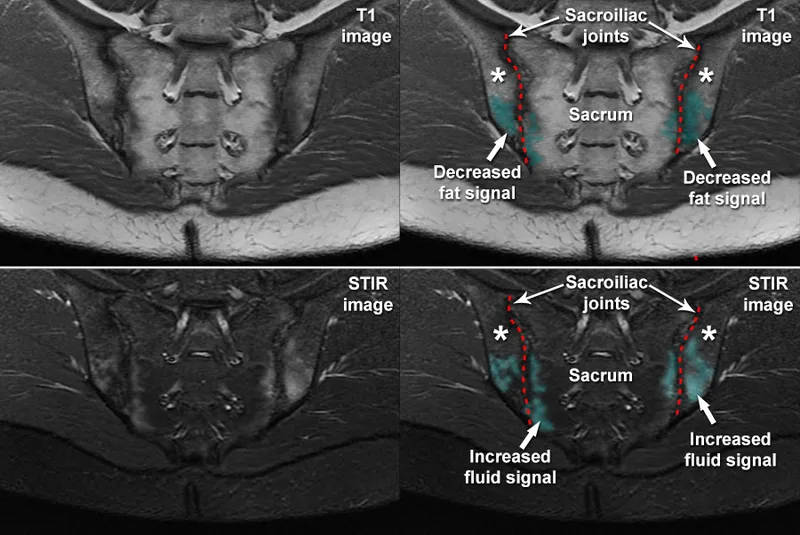

- Imaging: Sacroiliitis on X-ray or MRI. Advanced ankylosing spondylitis may show "bamboo spine."